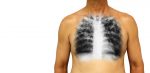

Инфильтрация легких – клинический синдром, при котором происходит замещение нормальной воздушности легочной ткани патологическим субстратом повышенной плотности, чаще всего воспалительного характера. При этом в паренхиме легких образуется участок, характеризующийся увеличенным объемом и повышенной плотностью, а также скоплением несвойственных ей клеточных элементов.§ СодержаниеПричиныКлинические признакиДифференциальная диагностика легочных инфильтратовСиндром инфильтрации легких при крупозной пневмонииИнфильтративная форма туберкулезаЭозинофильный легочный инфильтратПневмония … Читать далее Инфильтрация легких: что это такое